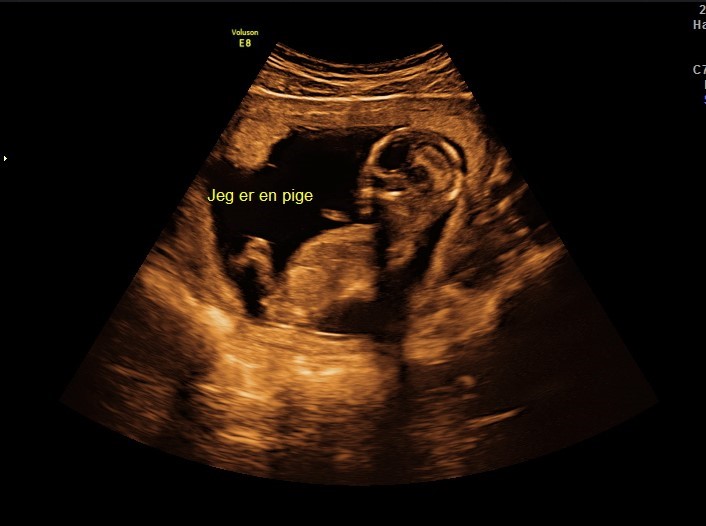

Vores lille bandit ville ingenting da vi var til kønsscanning(14+3), men så lige pludselig var der bare kønsdel på hele skærmen

Vi er i hvert fald ikke i tvivl (selvom hun snød og skrev det på skærmen)